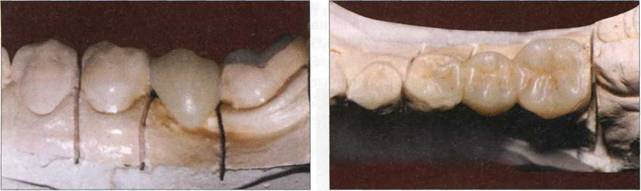

Рис. 895. Композиционная конструкция в области нижней челюсти слева (вестибулярная поверхность) на гипсовой модели

Рис. 896. Композиционная конструкция в области нижней челюсти слева (жевательная поверхность) на гипсовой модели

Рис. 897. Композиционная конструкция в области верхней челюсти слева (вестибулярная поверхность) на гипсовой модели

Рис. 898. Композиционная конструкция в области верхней челюсти слева (жевательная поверхность) на гипсовой модели

Изготовлены рабочие разборные модели из супергипса. Опорные зубы изолированы лаком. По общепринятой методике производится адаптация шнура "GlasSpan" в слой жидкоте-кучего композита фирмы "3M-ESPE", нанесенного в полости опорных зубов. Светополиме-ризация на модели. Осуществляется послойная моделировка отсутствующих тканей, с восстановлением фиссурно-бугорковых контактов, шлифовка, полировка. Этап полимеризации также осуществлен в аппарате "Targis Power" фирмы "IVOCLAR".